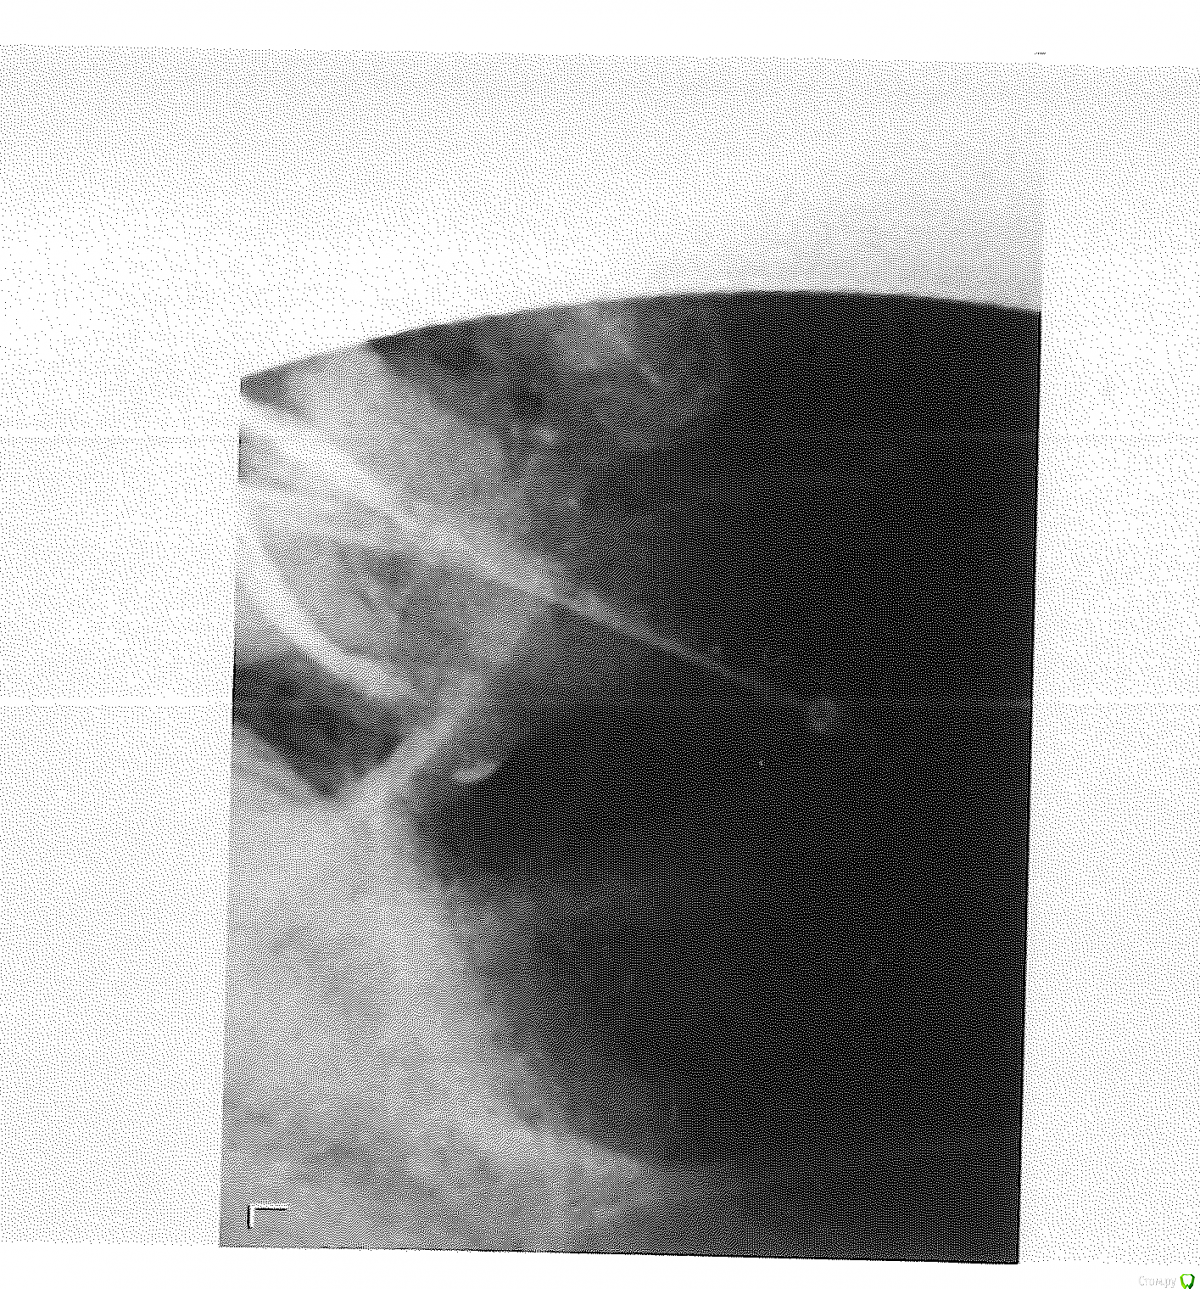

kvazisp Опубликовано 6 мая, 2015 Автор Поделиться Опубликовано 6 мая, 2015 (изменено) Вот такое вот фото у меня есть. Качество не ахти. Буду признателен за комментарии. Изменено 6 мая, 2015 пользователем kvazisp Ссылка на комментарий

kvazisp Опубликовано 7 мая, 2015 Автор Поделиться Опубликовано 7 мая, 2015 После. Но еще не закрыто (временная пломба) Ссылка на комментарий

Гарриевич Опубликовано 27 мая, 2015 Поделиться Опубликовано 27 мая, 2015 при лечении коффердам не использовалсяпломбировка каналов не четкая и не однородная Ссылка на комментарий